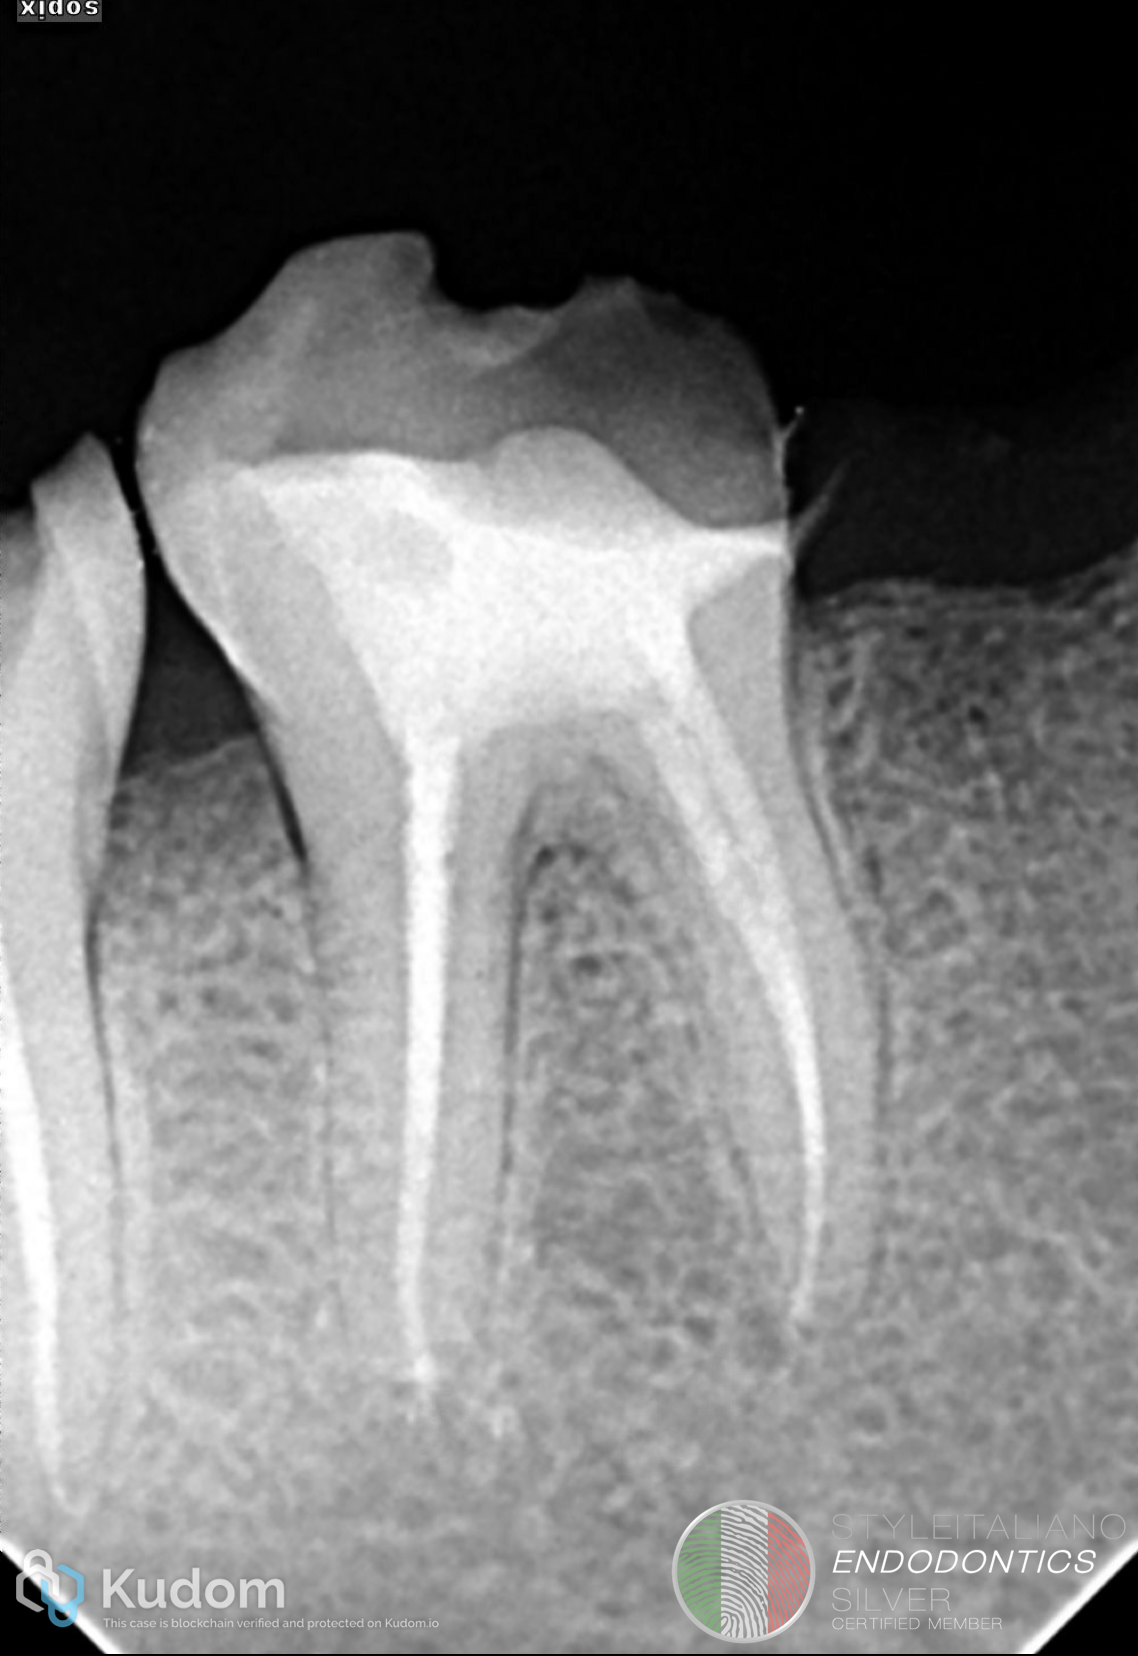

Fig. 5

Obturation

Following the shaping, the canal system was obdurated using a bioceramic- based obturation technique, ensuring optimal sealing ability and biological compatibility.

Bioceramic materials offer superior flow, chemical bonding to dentin, and bioactivity making them particularly advantageous in complex and calcified anatomies where conventional sealing may be compromised

Fig. 6

A shifted angulation radiograph was taken to enhance anatomical interpretation. The mesial canals demonstrated a type II configuration, where two canals join into a single pathway apically. Similar, the distal communication between the distal canals.

The angulated view was essential in revealing the true canal anatomy, which was not clearly evident in the initial straight projection.